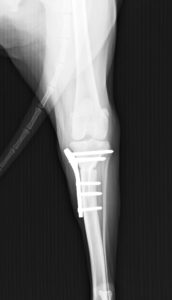

ジャンプした拍子に右後肢跛行とのことでかかりつけ医を受診後、セカンドオピニオンとして当院の整形外科に来院されました。若い雄猫に多く見られる「大腿骨頭すべり症」と診断。ご家族様と相談の上、骨頭切除を実施しました。経過は順調でしたが、その6ヶ月後に逆側も同様に骨折し、同治療を行いました。結果的に両側の骨頭切除が行われましたが、経過は良好です。